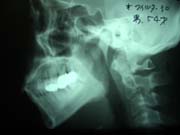

【パノラマレントゲンとセファロ】

当院では、顎関節症の治療にも力を入れております。

セファロという医療機器により、鮮明な顎関節の画像を撮影することができますので、効果的な治療が可能です。

顎関節症は放っておくとますます症状が悪化します。まずは当院にお気軽にご相談下さい。

※下の顎関節の画像の掲載につきましては、患者様のご了承を頂いております。

〜顎関節〜